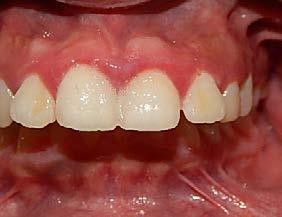

Figura 12. Panorámica de progreso. Figura 13. Frente, derecha e izquierda de progreso

En los estudios intraorales de progreso en la fotografía de frente se observa la mejoría el overjet y overbite (Figura 13), así como la coincidencia de las líneas medias dentarias. Se obtuvo las relaciones clases I caninas y molares para la obtención de la máxima intercuspidación, y para el paralelismo radicular se utilizaron arcos de acero, así como la oclusión funcional, con el detallado rectangular 0.019 × 0.025 superior e inferior, dobleces de primer, segundo y tercer orden y elásticos en W.

Se logró la corrección del overjet , overbite y la coincidencia (Figura 16) de las líneas medias dentarias, cierre del espacio anterosuperior.